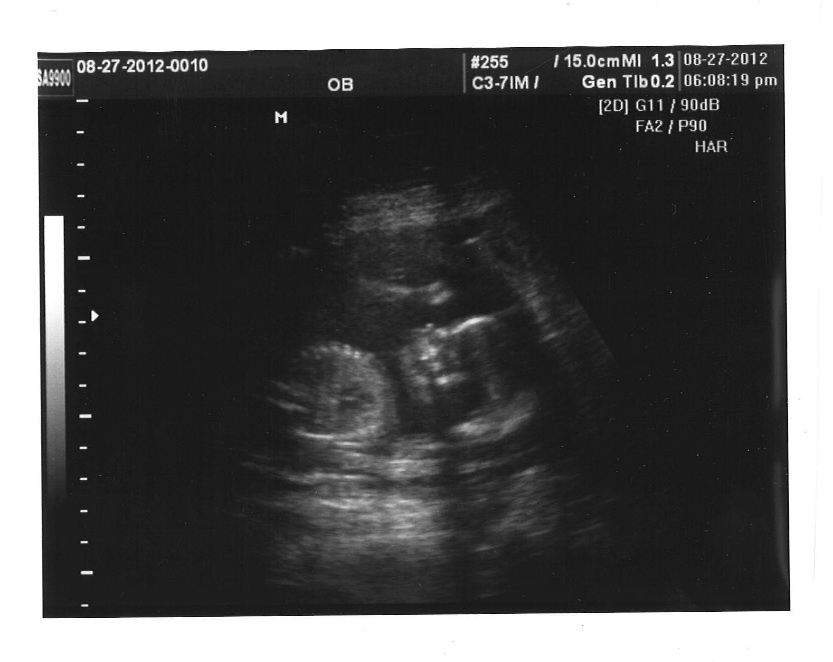

But it's confirmed ladies, IT'S A GIRL!!!!!!! :running:

There were three lines the whole time... nothing between her little legs!